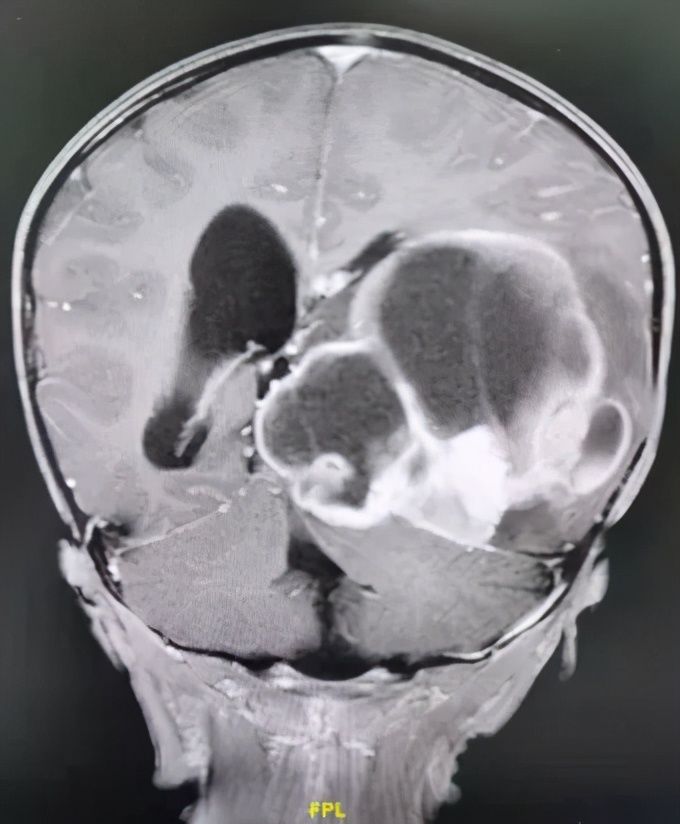

五一假期刚结束,付先生夫妻怀抱2岁儿子小烨,怀着最后一丝希望匆忙赶到中肿找到王翦主任医师。通过仔细检查,王翦主任医师初步判定小烨颅内巨大肿物位于左侧颞顶枕叶,性质考虑恶性室管膜瘤可能性大。肿物巨大,直径达11cm,除了破坏左侧颞顶枕叶脑组织,累及脑室系统并将呼吸和心跳中枢脑干往右侧推移2cm,颅高压明显,随时都可能有生命危险。

脑和心脏一样都是单器官,不同部位的脑有不同的功能,精准调控着人类大部分的身心活动。2岁的小烨头颅最长径15cm,而脑内的肿瘤侵犯了左侧颞顶枕叶等,直径达恐怖的11cm,几乎波及整个左侧大脑!手术是最关键的救命手段,但脑内肿瘤异常巨大,备受病痛折磨的小烨体重仅有11公斤,机体代偿功能非常不完善,手术面临出血性休克、失语和肢体肌力下降等巨大风险。但看着付先生夫妻渴望而无助的眼神,王翦主任医师又一次下决心收治了这一辗转两广多家医院的疑难病例。

术前MR:头的最大直径15cm,而肿瘤直径达到了惊人的11cm